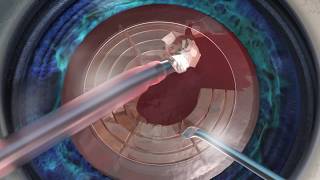

The LensX Laser Procedure (Cataract Surgery) video

LenSx Laser Cataract Surgery Video The LensX Laser Procedure (Cataract Surgery)

Laser-Assisted Cataract Surgery (LenSx) with Dr. Grover Robinson IV Watch live surgery using the laser cataract system - how does it work? Eye News TV